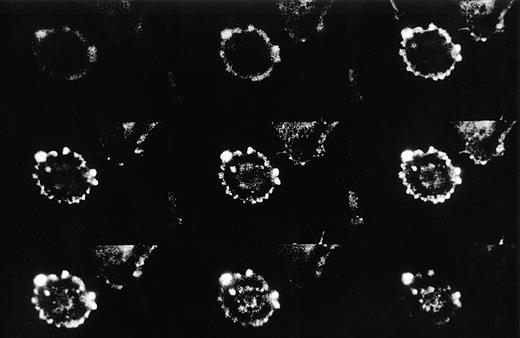

The observation that GAS6 did not inhibit adhesion driven by IL-8 and FMLP, which exert their effect by activating the PMN adhesive machinery, suggested that GAS6 acts on EC and not on PMN. To assess this possibility, we evaluated the GAS6 effect on PMN adhesion to FCS-coated culture wells. In this experimental system, PAF potentiated PMN adhesion, but GAS6 did not inhibit the PAF-driven adhesion (Fig 3). Moreover, to confirm the action of GAS6 on EC, we pretreated EC with GAS6 for 10 minutes and with PAF for an additional 10 minutes. EC were then washed three times and PMN were seeded. These experiments showed that the inhibitory effect of GAS6 on PAF-driven PMN adhesion to EC was unmodified by washing (data not shown). Titration experiments showed that high concentrations of rhGAS6 were needed to inhibit PMN adhesion to PAF-treated EC, and that inhibition was dose-dependent in the concentration range between 0.1 and 1 μg/mL (Fig 4). One possibility was that high concentrations of rhGAS6 were needed to overwhelm the effect of endogenous GAS6 produced by EC themselves. To assess this possibility, we evaluated the effect of a soluble ligand of GAS6 on PMN adhesion to EC. EC were treated or not for 10 minutes with a soluble form of Axl (Axl-x),15 and PMN adhesion was then assessed. Treatment of resting EC with Axl-x significantly potentiated PMN adhesion (Fig 5). These data suggested that GAS6 endogenously produced by resting EC functions as an antiadhesive molecule. We also investigated if EC activation by proadhesive factors modulates GAS6 expression by these cells. To assess this hypothesis, EC were treated or not with PAF, fixed, permeabilized, stained with the 3C12 MoAb, and examined by confocal microscopy. The fluorescence distribution pattern was rather granular, mainly organized in filament-like structures throughout the cytoplasm (Fig 6). In a proportion of EC, fluorescence localization was markedly different clustered in small patches close to the cell surface (Figs 6 and7). In PAF-treated cells, the fluorescence intensity was markedly lower and displayed a diffuse, granular pattern only with no evidence of surface patches (Fig 6). Moreover, analysis of unpermeabilized cells by immunofluorescence and FACS analysis showed that GAS6 is expressed on the surface of a variable proportion of resting EC (20% to 50%) and that treatment with PAF decreased surface expression of the molecule (data not shown).

Perimembrane localization of GAS6 in a resting EC. EC on glass coverslips were fixed, permeabilized, and immunostained as described in Materials and Methods. The individual frames obtained following confocal microscopy analysis of 1-μm intervals along the Z axis are progressively depicted from left to right and top to bottom. The first frame refers to the section taken at the glass attachment. One typical example is shown.